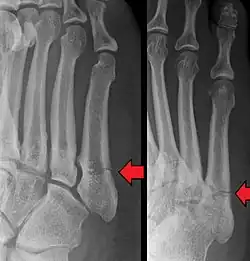

Example of Robert Jones' Jones fracture

1896 and 1902 – Jones fracture and published radiograph

On 7 February 1896, Welsh orthopaedic surgeon Robert Jones (and Oliver Lodge) took a radiograph of the wrist of a 12-year-old boy to locate a bullet that could not be found by probing. The X-ray required a 2-hour exposure, but successfully demonstrated the bullet lodged in the third carpometacarpal joint. This case was published in The Lancet in February 1896,[30] the first published clinical radiograph.[31]

Robert Jones described the fracture of the fifth metatarsal which bears his name in the Annals of Surgery in 1902. In his paper, Jones described the fracture in a series of six patients, the first of which was himself.[32]